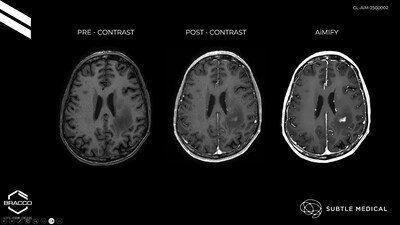

AiMIFY™ AI MRI Software Earns CE Mark, Backed by Bracco and Subtle Medical

AI-powered solution aims to improve image quality and efficiency in MRI workflows across Europe...